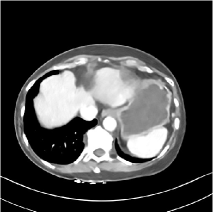

Refer to caption

Fig. 4: FBP images of test examples.